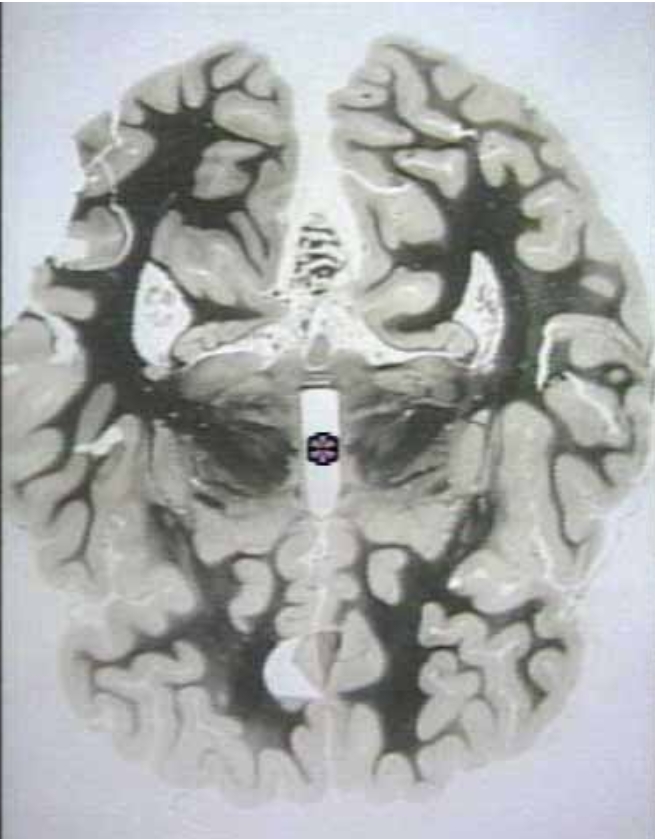

What is the arrow pointing at?

Thalamus (Frontal section view)